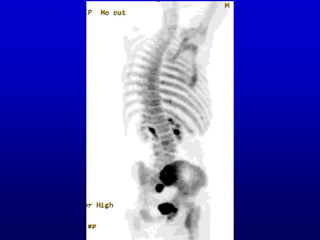

Next I will show you a rotating 3D

display called a MIP, from a 3D

bone scan of a patient with a lesion

in one sacroiliac joint (among a

number of abnormalities). Then I

will ask you whether it is the right or

left sacroiliac joint. I would not

strain your brain about this, just

form an impression without

enduring great anxiety over

whether it is correct or not.

Next I willshow you a rotating 3D display called a MIP, from a 3D bone scan of a patient with a lesion in one sacroiliac joint (among a number of abnormalities). Then I will ask you whether it is the right or left sacroiliac joint. I would not strain your brain about this, just form an impression without enduring great anxiety over whether it is correct or not.

• #7 You should get a sense of 3D, which is the point, and you should see that one of the sacroiliac joints has a much more intense signal (that is, darker) than the other. Is it the left of the right?